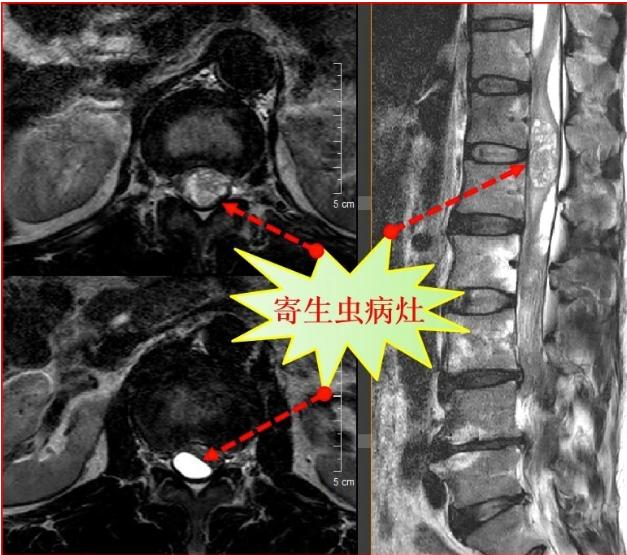

描述:近日,一位男子在醫(yī)院接受治療,引起了廣泛關(guān)注。據(jù)悉,該男子長(zhǎng)期以來有著一個(gè)不尋常的嗜好,每天堅(jiān)持吞食蛇膽并飲用蛇藥,結(jié)果竟然導(dǎo)致他15年后突發(fā)重病。這一離奇的案例引發(fā)了醫(yī)學(xué)界的深思和警醒,大家紛紛呼吁我們要更加珍惜生命,正確看待養(yǎng)生方式。

然而,好景不常,命運(yùn)似乎對(duì)他開了一個(gè)惡作劇的玩笑。近日,他突發(fā)劇烈腹痛,隨即被緊急送往醫(yī)院。經(jīng)過詳細(xì)的檢查和專家的診斷,醫(yī)生們愕然地發(fā)現(xiàn),他的膽囊中充滿了結(jié)石,嚴(yán)重影響了正常排泄功能。

有關(guān)專家表示,長(zhǎng)期吞食蛇膽和飲用蛇藥,雖然在一定程度上可以起到提高免疫力的作用,但是其中所含有的毒素和化學(xué)物質(zhì),同樣會(huì)對(duì)人體的內(nèi)臟器官產(chǎn)生不可逆轉(zhuǎn)的傷害。尤其是膽囊作為排毒器官,接受過多的毒素刺激后會(huì)產(chǎn)生結(jié)石等并發(fā)癥,嚴(yán)重危害人體健康。